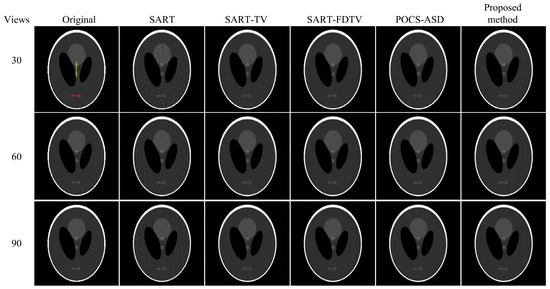

3.1. Digital Phantom

| Number of Views | Index | SART | SART-TV | SART-FDTV | POCS-ASD | Our Algorithm |

|---|---|---|---|---|---|---|

| 30 | PSNR | 23.7308 | 23.9988 | 24.1963 | 24.0068 | 24.2794 |

| SSIM | 0.8399 | 0.9077 | 0.9359 | 0.9320 | 0.9498 | |

| 60 | PSNR | 22.4447 | 24.2463 | 24.4704 | 24.2596 | 24.5714 |

| SSIM | 0.7556 | 0.9176 | 0.9406 | 0.9378 | 0.9500 | |

| 90 | PSNR | 21.8542 | 24.3237 | 24.4957 | 24.3218 | 24.5829 |

| SSIM | 0.7037 | 0.9325 | 0.9484 | 0.9480 | 0.9516 |